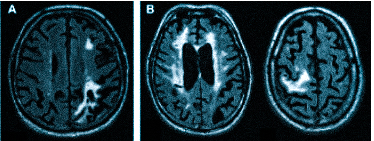

Множественные ишемические очаги при сосудистой деменции на МРТ: отсутствие памяти на недавние события и неадекватное поведение не являются признаками старости, своевременная диагностика деменции и патогенетическая терапия помогут замедлить прогрессирование болезни

демиелинизацию при рассеянном склерозе и иных атрофических процессах;

-

Что покажет МРТ головы с контрастом

После контрастирования при МРТ детализация мелких структур значительно выше. Магнитно-резонансную томографию с усилением предпочитают онкологи, так как можно увидеть контуры опухоли, определить степень ее инвазии (прорастание в близлежащие ткани), диагностировать метастазы. МРТ с введением контраста лучше показывает изменения после операции, патологические очаги в головном мозге на фоне рассеянного склероза, при болезни Альцгеймера. Чаще используют препараты на основе хелатов гадолиния. Мировая практика подтверждает высокий профиль безопасности: при грамотном применении осложнения встречаются крайне редко.